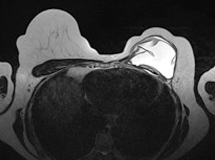

Der wesentliche Unterschied zu anderen MRT-Untersuchungen besteht darin, dass die Patientin auf dem Bauch liegt und die Brust hängend in einer speziellen Brustspule positioniert wird. Der Kopf wird ähnlich einer Massageliege auf einem weichen Kissen gelagert, die Arme liegen an der Seite des Körpers. Da das MRT-Gerät während der Untersuchung verursacht, werden Ihnen Kopfhörer zum Schutz Ihres Gehörs aufgesetzt. Bei Patienten mit starker Platzangst können wir mit Hilfe eines Medikaments (Diazepam) eine leichte Ruhigstellung bewirken. Während der Untersuchung wird Ihr Wohlergehen über Monitore permanent überwacht. Bei Unwohlsein oder Ängsten können Sie sich leicht bemerkbar machen, damit unsere Mitarbeiterinnen zu Ihnen kommen.

Für die Untersuchung werden zunächst Schnittbilder ohne Kontrastmittel angefertigt. Um die Lage und Unversehrtheit von vorhandenen Brustimplantaten zu überprüfen, werden spezielle Schichtführungen und Sequenzen verwendet. Anschließend wird das Kontrastmittel über die zuvor eingebrachte Nadel verabreicht und Schnittbilder nach Kontrastmittelgabe angefertigt. Insbesondere für die Erkennung von Brustkrebs ist der Einsatz von Kontrastmittel zwingend notwendig. Die gesamte Untersuchung dauert ca. 20 Minuten.